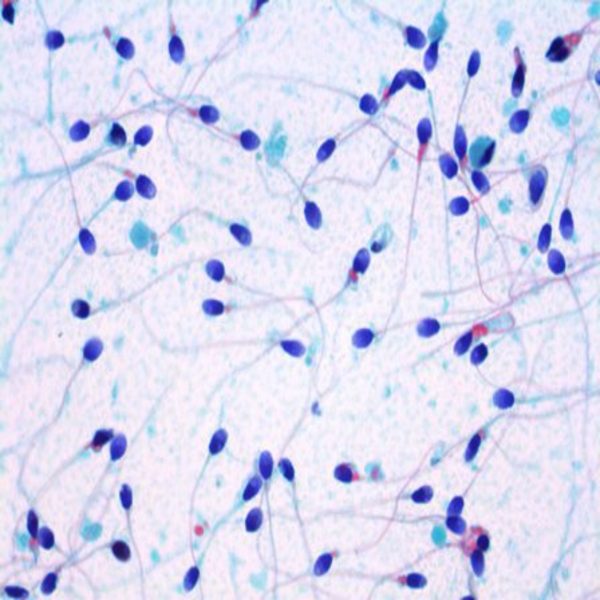

- General and specialized tissue and cell staining

Histological methods includes sample processing in the pathology laboratory, preparation of the slide and its examination under a microscope, sample fixation, molding, microtome cutting, staining and assembly of the slides.